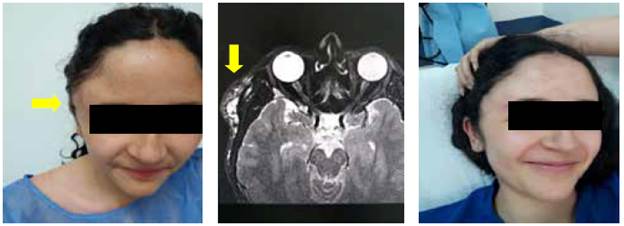

Las malformaciones linfáticas, que la literatura denomina higroma quístico o linfagioma, se diagnosticaron en 12,5 % de casos, la mayoría en niños pequeños, y su localización más frecuente es la cabeza y el cuello (figura 1). Tienen mayor recidiva con manejo quirúrgico y mejores resultados con los procedimientos percutáneos 10 (figura 2).

Figura 1 Malformación linfática en cuello. A) Aspecto al examen físico donde se aprecia que la masa aumenta con las maniobras de Valsalva. B) Resonancia nuclear que muestra hipercaptación de lesión linfática.

Figura 2 Paciente con malformación vascular en región temporal derecha con deformidad estética y dolor, manejada con alcohol absoluto vía percutánea. A) Aspecto previo a la intervención. B) Resonancia magnética nuclear donde se aprecia la lesión. C) Aspecto de la paciente al segundo mes después del tratamiento.